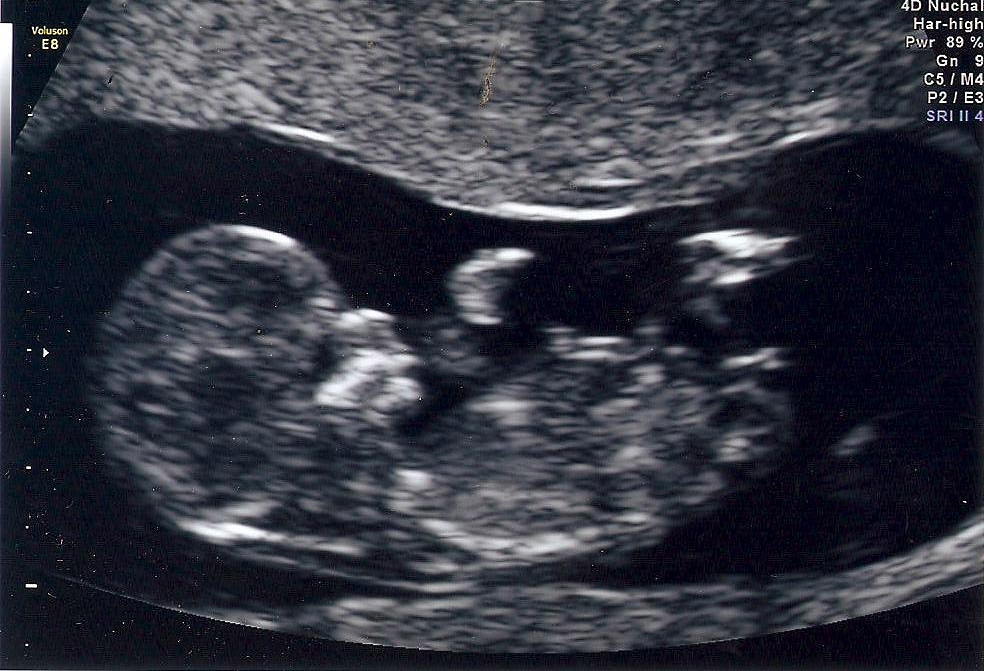

Doughies has been on a bit of a go slow since Abs (head baker) has been focusing on an altogether different type of baking – no yeast or flour here – we have a wee bairn due May 8th, which is creeping perilously close…